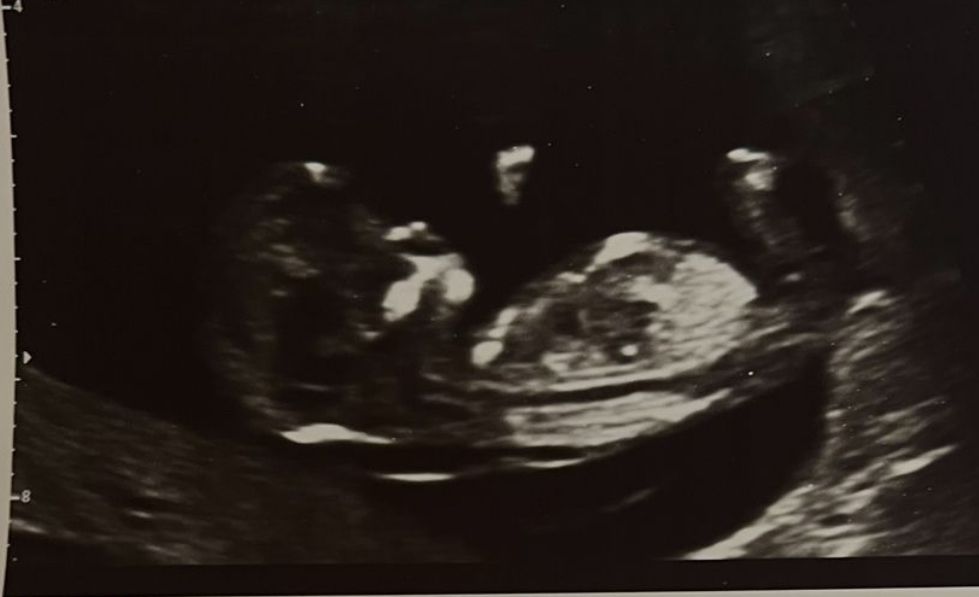

Не видно даже толком как располагается половой бугорок. На этом сроке только под углом градуса можно примерно прикинуть кто будет. Если бы на втором фото видно было бы бугорок, примерно можно было предположить. Но так как не видео, можно просто по угадывать

Алина Долгачева, как она могла предположить по данным фото, я без понятия. Врач у себя на мониторе видел расположение полового бугорка и примерно прикинул, кто может быть. Вот так под определенным градусом примерно предполагают кто будет Изображение

Со стороны попы у них одинаково на этом сроке, смотрят угол наклона бугорка в положении, как второе фото. Тут он закрыт ножкой, увы. Не видно